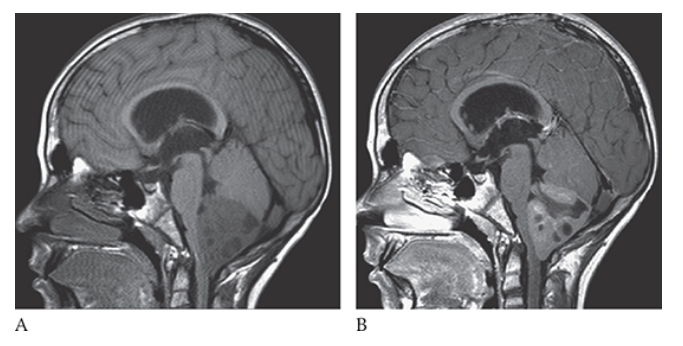

Medulloblastoma. Axial T2W image shows hyperintense cystic areas within the mass.